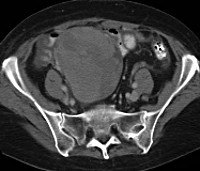

Используйте УЗИ брюшной полости, трансвагинальное, ректальное тазовое с цветной допплерометрией. Признаки метастазирования яичников - четкие контуры и неоднородная структура опухоли, плотные кровеносные сосуды, наличие экссудата в брюшной полости.